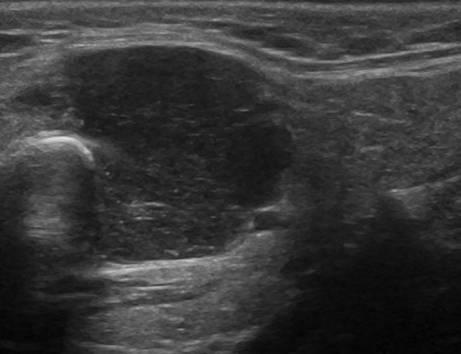

U tuyến nước bọt

» Thông tin: Nam giới – 63 tuổi.

» Lâm sàng: Khối vùng góc hàm.

# Lymphoma tuyến nước bọt dưới hàm.